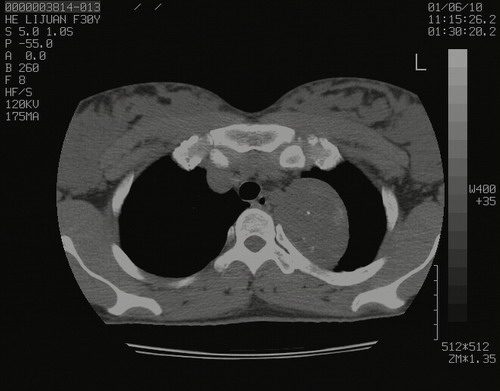

怀孕3个月时(2009-3至4月间),自述突感左侧前后胸疼痛1天,以前胸明显,随后偶感闷痛,余未见异

左肺尖脊柱旁沟肿块,境界清楚,边缘光滑,密度不均,内有多发点片状钙化,考虑良性肿瘤,骨软骨瘤或神经源性肿瘤可能,肺错构瘤不除外。

左后上纵隔见一类圆形肿块影,外侧边界清,密度不均匀,内可见点状钙化影,增强呈不均匀强化,考虑神经源性肿瘤可能。期待病理结果。